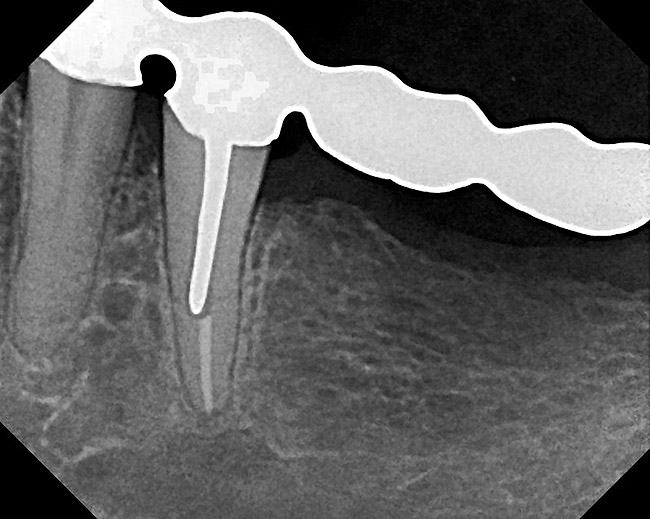

Figure 18  Radiographic examination after smoothing and blending of the bony surfaces confirmed that the bone was smooth and the ledge was eliminated.

Figure 18

Figure 22  Radiograph taken 8 weeks after closed-flap resective surgery was performed. Note that the bony contour was good, but some minor unevenness was apparent.

Figure 22

Figure 23  Radiograph taken 6 months after resective surgery and placement of the definitive prosthesis. Note how the bony crest remodeled and was much smoother than seen in the 8-week postoperative radiograph. By making the surgical correction using the closed-flap technique at the time of preparation and impression taking, a significant amount of operative time (> 6 months) was saved and an excellent biologic result was achieved.

Figure 23